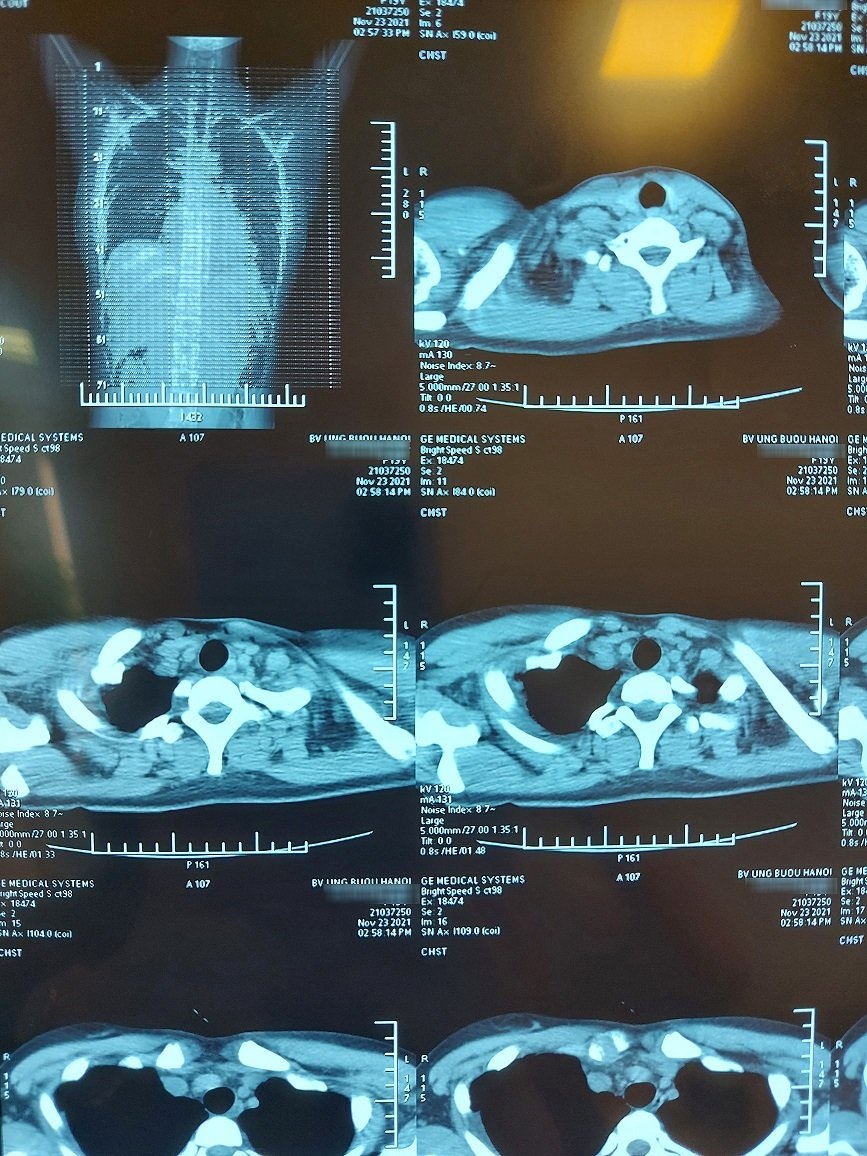

Khi đi khám tại Bệnh viện Ung Bướu Hà Nội, bệnh nhân được phát hiện có khối u lớn trong lồng ngực.

Khối u quái có đường kính khoảng 20 cm, nặng hơn 1kg đã đè đẩy tim, chèn ép làm xẹp phổi, dính nhiều cơ quan nội tạng xung quanh.

Vị trí u nằm ở trung thất trước trên bên phải, tổ chức u có cả lông, tóc, mỡ, xương. Khối u to, đè đẩy tim, chèn ép làm xẹp phổi, dính nhiều cơ quan nội tạng xung quanh.